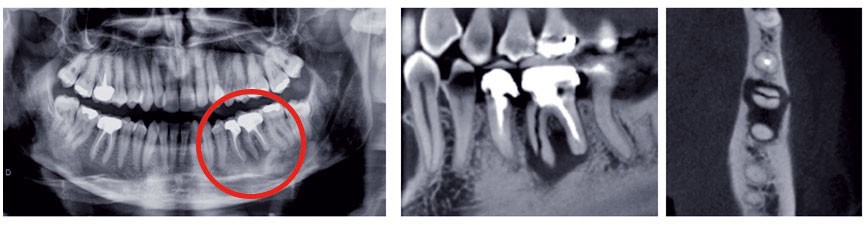

L’imagerie moderne (3D)

Initiée par le scanner Rx, complétée par le Cone Beam, elle restitue le volume anatomique dans ses trois dimensions par calcul informatique. Les principes d’acquisition sont…